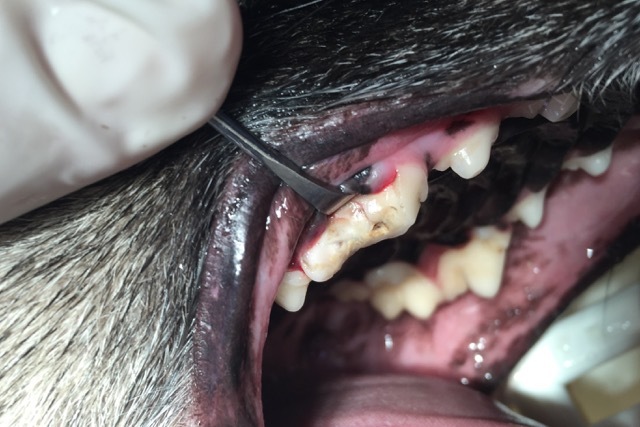

Seit einigen Tagen war sie darüber hinaus auch ruhiger geworden und zog sich immer mehr zurück. Die Untersuchung der Maulhöhle und der Zähne brachte schnell ans Tageslicht, was die Ursache dafür war. „Lotte“ hatte Zahnschmerzen, und das wohl schon seit einiger Zeit. Der Reißzahn im rechten Oberkiefer war schon vor längerem abgebrochen, was man an der dunklen Verfärbung an der Bruchstelle erkennen konnte (Foto 1). Auch ein unangenehmer, modriger Geruch machte sich beim Öffnen des Fanges im Behandlungsraum breit. Der Zahn war abgestorben und durch den offenen Wurzelkanal waren Bakterien in die Tiefe gelangt, die eine schmerzhafte Entzündung des Kiefers verursacht hatten. Schnell musste der Hündin geholfen werden.

Bei „Lotte“ lag jedoch eine komplizierte Fraktur mit gespaltener Krone vor, so dass tatsächlich nur eine Extraktion des Zahnes in Frage kam. Solch ein dreiwurzeliger Zahn kann nicht im Ganzen gezogen werden. Die Wurzeln sitzen fest im Kiefer und sind gerade bei schon älteren infizierten Zähnen sehr spröde und morsch und brechen leicht in der Tiefe ab. Daher ist eine kieferchirurgische, offene Extraktion die Methode der Wahl. So wurde bei „Lotte“ die Mundschleimhaut um den Zahn herum gelöst und der Kieferknochen freigelegt. Dann wurde der Knochen mit einem wassergekühlten Bohrer über den Zahnwurzeln entfernt, bis diese komplett sichtbar waren. Anschließend wurde der Zahn mit einem Fräser in drei Teile geteilt und die einzelnen Wurzeln mit verschiedenen Hebeln gelockert, um sie danach separat ziehen zu können (Foto 2). Besonders wichtig ist es, dass keine Wurzelreste im Kiefer verbleiben, denn diese verursachen weiterhin Schmerzen und führen zu einer Abszessbildung im Kieferknochen. Nach Glättung der scharfen Knochenkanten wurde die Schleimhaut wieder über die Wunde gelegt und mit einer Wundnaht mit Einzelheften eines resorbierbaren Nahtmaterials verschlossen, welches sich nach einigen Wochen von selbst auflöst (Foto 3).